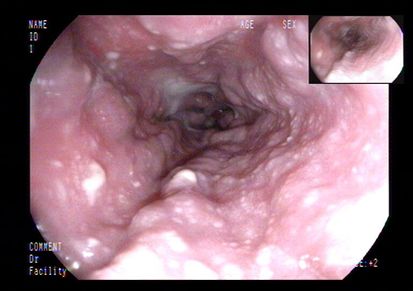

初步诊疗过程:入院后检查:血常规:单核细胞百分比 10.10%,淋巴细胞百分比 19.40%;尿常规:尿蛋白 +-;粪常规未见异常;肝功能:总胆红素 22.10umol/L,直接胆红素 12.83umol/L,谷丙转氨酶 88IU/L,谷草转氨酶 107IU/L,总蛋白 43.8g/L,白蛋白 24.3g/L,球蛋白 19.5g/L,总胆汁酸 31.4umol/L;血脂:总胆固醇 1.64mmol/L;电解质:钙 1.81mmol/L,磷 0.77mmol/L;凝血:凝血酶原时间测定 15.5秒,凝血酶原时间比值 1.46,活化部分凝血活酶时间测定 37.5秒,D-二聚体 3110.00ug/L,纤维蛋白(原)降解产物 9.56mg/L;肿瘤标志物:糖类抗原125 303.60U/ml,余项基本正常;肝炎系列+HIV+TP、T-SPOT阴性;腹水肿瘤标志物:糖类抗原125 390.10U/ml;腹水结核分枝杆菌IgG抗体阴性;复查腹水常规、生化仍提示漏出液;腹水培养阴性;PPD试验阴性;自身抗体系列未见异常。腹部超声:脂肪肝、胆囊壁毛糙、腹水;腹部血管彩超:肝段下腔静脉、门静脉及肝静脉内未见明显栓子回声。肝纤维化无创检测示:硬度值 36.5kPa。胃镜检查:食管静脉曲张、门脉高压性胃病、十二指肠多发溃疡。初步诊断为肝硬化失代偿期。给予利尿、抗感染、保肝、补白蛋白、放腹水、抑酸等治疗。患者病情无改善。

上消化道内镜: